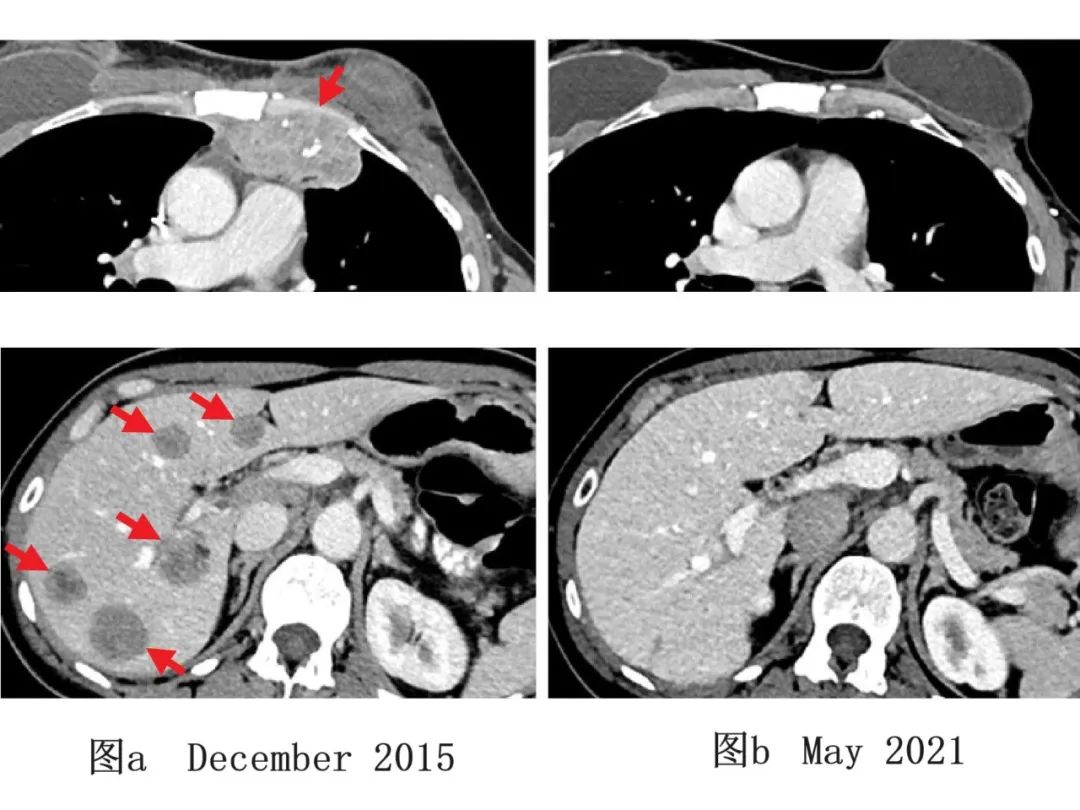

图4 一例乳腺癌患者TILs治疗前后影像学变化

图a:该患者治疗前(2015年12月)影像学检查示,患者胸壁(上,左)、肝脏(下,左)处,均有转移性病变。

图b:该患者经免疫治疗后(2021年5月)影像学检查示,患者肿瘤完全缩小,随访5年未出现新发癌症。